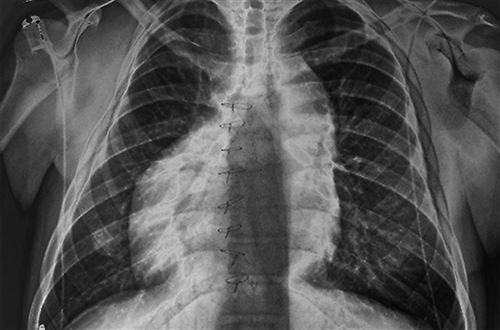

X光片显示,因不对称发育,人体的心脏和其他器官出现了位置错误。图片来源:ZEPHYR/SCIENCE SOURCE